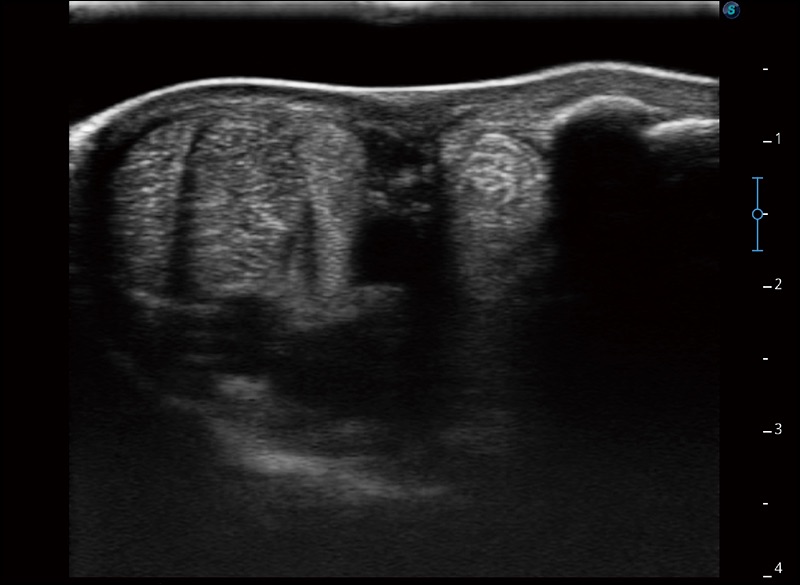

任意波束合成技术

在不牺牲时间分辨率的情况下提供出色的图像

空间复合成像

优化不同角度的图像